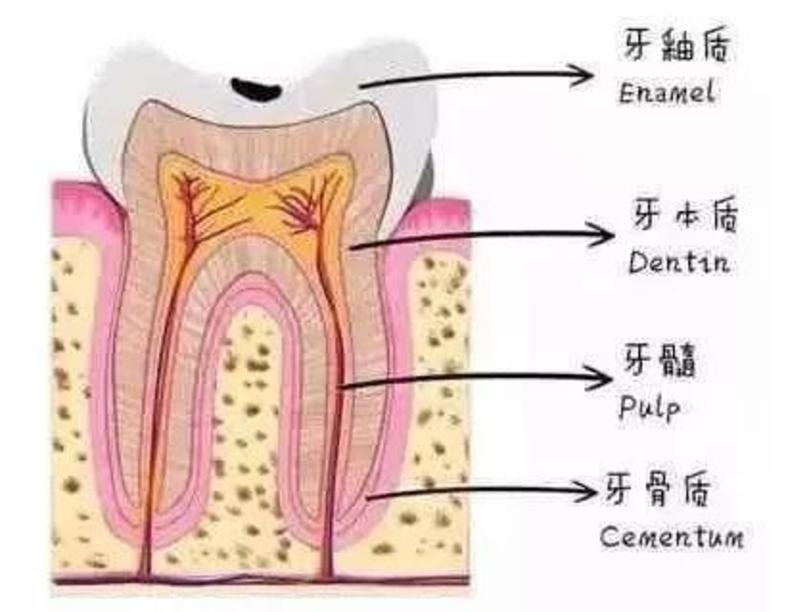

牙齿分为三层,最外层坚硬的牙釉质,不会感觉到疼痛;中间的牙本质能够感受到疼痛;最里层是敏感的牙神经,一受刺激便会疼痛难忍。